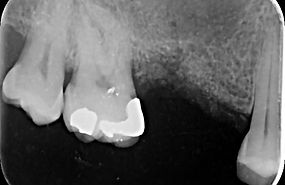

מקרה 1

גבר בגיל 50 ללא מחלות לא מעשן

הגיע למרפאתנו עם חוסר בשן מלתעה 15 וטוחנת 16

בצילום הסיטי ניתן לראות חוסר עצם

המגיע עד ל3 מ"מ בסינוס המקסילרי

חלל הסינוס נקי ללא פתולוגיות והוחלט על שיטות

והתקנת 2 שתלים IRAISE

עצם גרמית כ-3 מ"מ